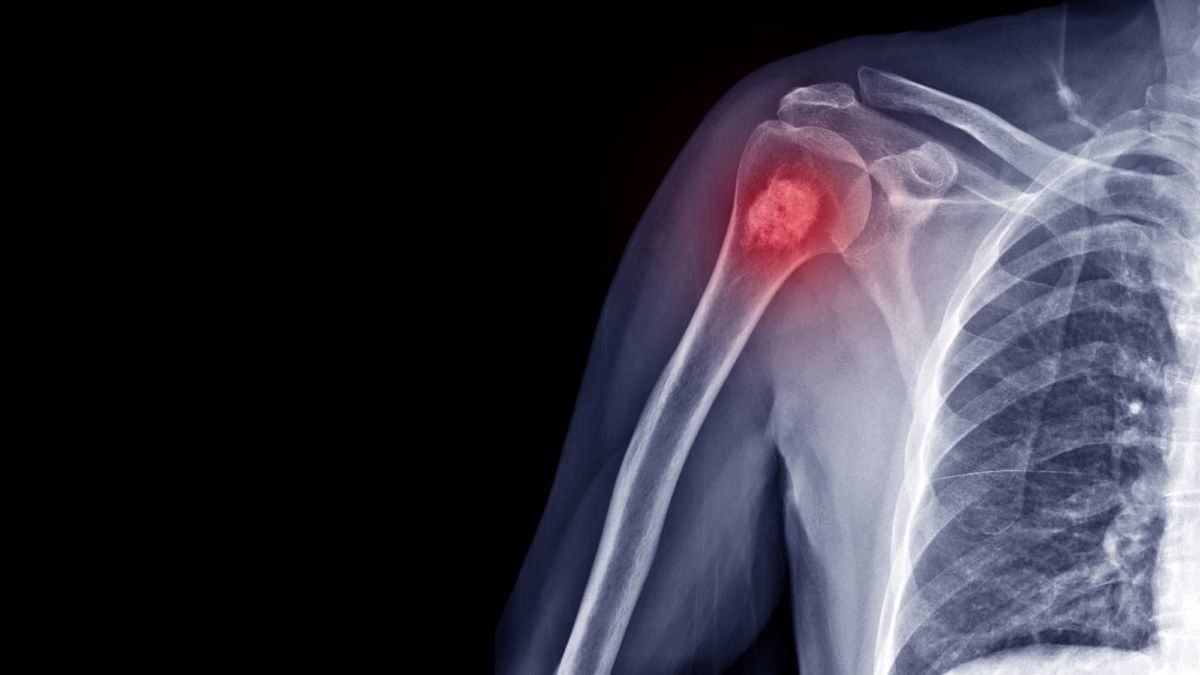

- Tumor jinak tulang: adalah pertumbuhan sel abnormal di dalam tulang. Tumor ini bisa bersifat jinak atau ganas. Tumor jinak tidak menyebar ke bagian tubuh lain dan biasanya tidak mengancam jiwa, tetapi bisa tumbuh besar dan menyebabkan masalah pada struktur tulang dan jaringan di sekitarnya.

- Kanker tulang: Kanker tulang adalah bentuk yang lebih serius, di mana tumor tulang bersifat ganas dan memiliki potensi menyebar ke organ lain (metastasis).